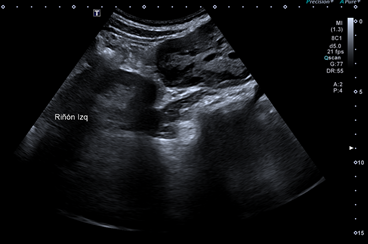

Se completa la exploración en la consulta de Atención Primaria, con ecografía a pie de cama donde se visualiza una imagen de ecoestructura heterogénea, con zonas hiperecoicas y zonas anecoicas, yuxtarrenal izquierda y que capta Doppler en algunas zonas.